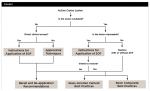

Background: Manufacturer instructions for 38% silver diamine fluoride (SDF) are limited to current FDA clearance for tooth desensitization. There is a need for instructions to provide best-practice recommendations for off-label use of SDF for caries prevention and arrest. Methods: The authors considered existing clinical approaches to the use of 38% SDF at pH 10 for the prevention and arrest of active dental caries, in light of the best current evidence. Application of SDF, with or without subsequent direct restoration, is included. The content was reviewed by stakeholders including but not limited to those listed on the consensus statement (Appendix A, below). Results: 38% SDF for the prevention and arrest of active caries lesions, as well as compatibility with common direct restorative materials, such as glass-ionomer cement and resin composite, has a foundation in the scientific literature. A practical decision-flow diagram and accompanying best practices for treatment of caries lesions, based on clinical access and intention to restore, were developed based on available evidence and expert clinical observation when no evidence was available. Conclusions: Based on the best available evidence, a logical approach can be adopted regarding the practical use of 38% SDF for caries prevention and arrest. Practical implications: SDF used as per these instructions for prevention on high-risk tooth surfaces and arrest of active caries lesions has a place in the practitioner's dental caries management armamentarium. When SDF is applied to active lesions, it can be used with or without subsequent restoration, depending on clinical context, expert judgment, and patient input.

Authors' note: Appendix A Consensus Statement, which appears at the end of this article, sets the stage for this review of silver diamine fluoride, and readers may benefit from reading it first. Additionally, the practical decision flow diagram (Figure 1) will be useful to readers, both in helping to organize consumption of this article's content as well as applying its content to clinical scenarios.

Because current US Food and Drug Administration (FDA) clearance for SDF is for treatment of tooth sensitivity (and not dental caries prevention or lesion arrest), there are no manufacturers' instructions for use of SDF to prevent or arrest dental caries lesions. Similar to fluoride varnish, this off-label use is permissible and appropriate under US law. This instructional article provides recommendations for the arrest and prevention of dental caries lesions using 38% SDF solution at pH 10 (Appendix B, SDF at a Glance) based on current available evidence. It should be noted that these instructions and protocols are not applicable nor intended for other products that contain a higher ammonia component and higher pH, which require a gingival barrier or dental dam to prevent soft-tissue burns,17 or the addition of potassium iodide. For reader convenience, a flow diagram of the clinical use of SDF on an active lesion has been developed and is provided (Figure 1). Subsequent sections of these instructions are section-titled to sync with the diagram. The flow diagram is reflective of the international consensus statements on carious tissue removal and when to intervene in the caries process,18,19 and is in accord with the original meanings of the terms "cavity" and "carious" as indicating that a full enamel cavitation is necessary for bacteria to infect the dentin and therefore possibly indicate invasive treatment.